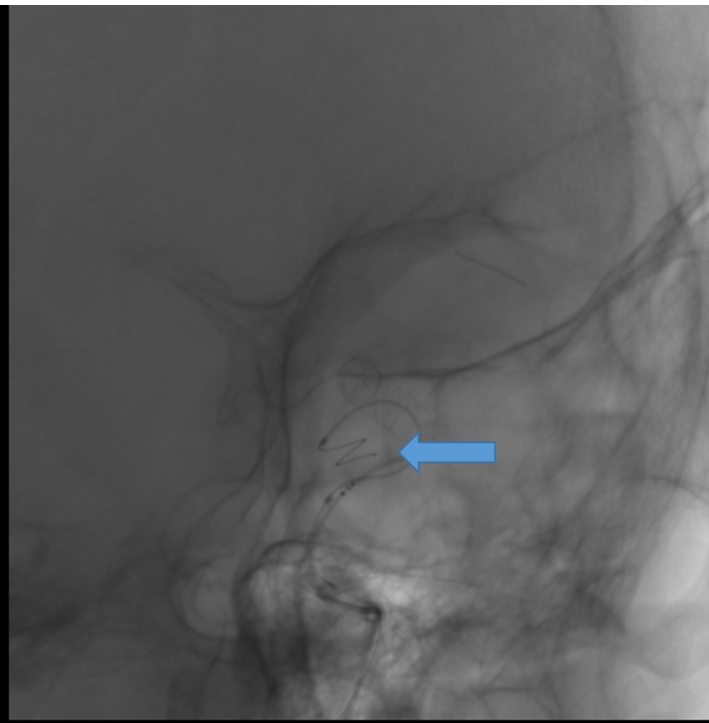

通过支架微导管,半释放支架(Lvis 5.5/30规格215530-CAS),首圈填入Nufairy™3D0730,箭头所指处为头端显影点,首圈在瘤内满意成篮。

图片